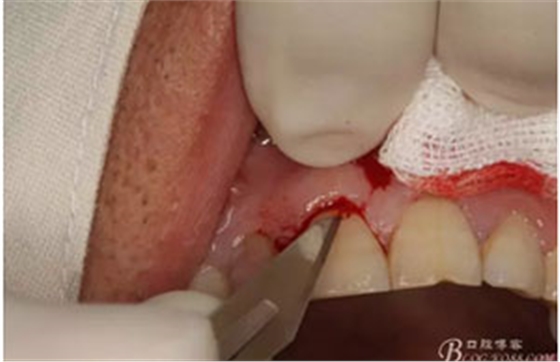

圖6.行唇側(cè)角形切口(11近中垂直切口+齦溝內(nèi)水平切口)垂直切口距離前庭溝約1~2mm。這樣可以減輕術(shù)后腫脹。

圖7. 角形切口中的齦溝內(nèi)切口情況:11號(hào)刀片伸進(jìn)齦溝內(nèi)斜切。